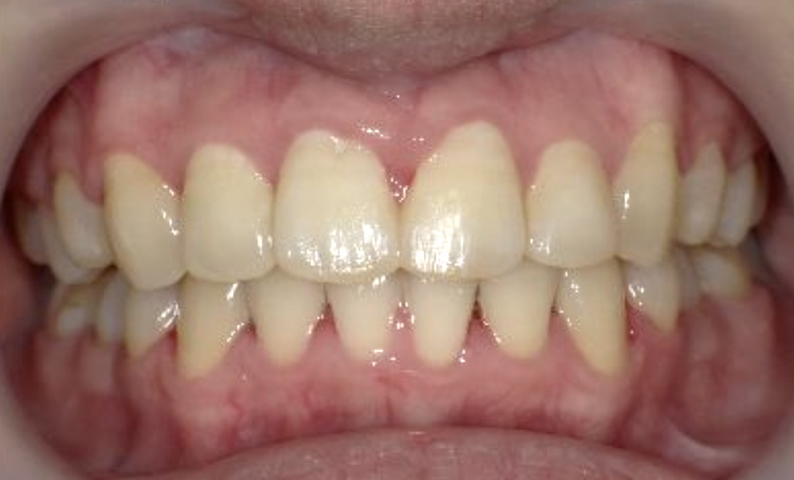

症例_025 上顎だけの部分矯正

治療期間:7ヶ月金額:30万円+税女性前歯のガタガタ上の前歯だけ

| Before | After |